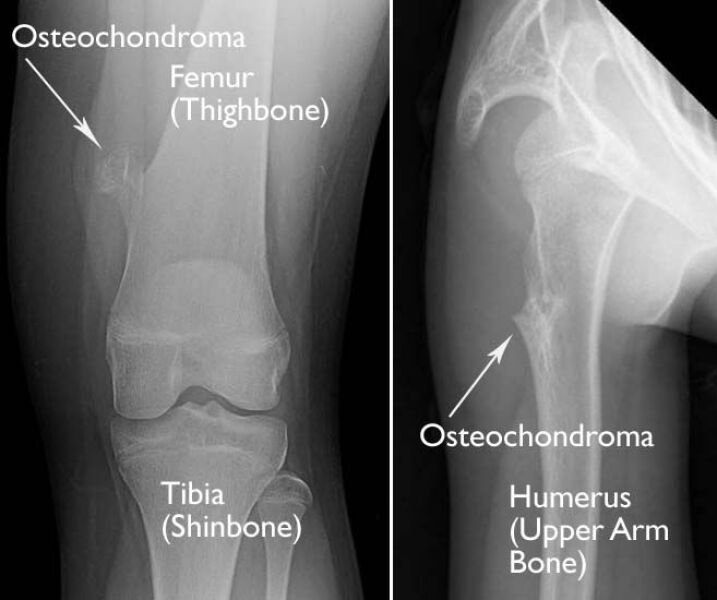

Could be an osteochondroma (benign bone tumour).

Not on both knees.

it sounds like it’s completely normal bony protrusions, probably the fibula as pp said.

These are examples of an osteochondroma. They normally start on the bone near a growth plate. One of my DC’s has one, had it x-rayed and checked out. Doesn’t give him problems but was advised to avoid contact sports.